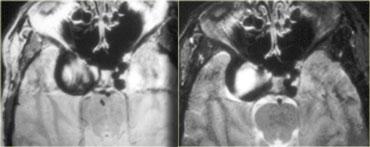

Trên các hình CT không tiêm và có tiêm thuốc cản quang ở góc trên bên trái, chẩn đoán phân biệt chính của khối ngấm thuốc bao gồm u màng não, u tuyến yên và phình động mạch.

Hình MRI sau tiêm thuốc tương phản từ ở góc trên bên phải loại trừ phình động mạch (không có hiện tượng mất tín hiệu do dòng chảy), tuy nhiên trên các hình cắt ngang, u tuyến yên và u màng não vẫn còn khó phân biệt.

Lưu ý sự lan rộng của tổn thương dọc theo màng não.

Tâm của tổn thương nằm phía trên hố yên.

Trên các hình cắt coronal (T1W và T1W sau tiêm thuốc tương phản từ), có thể nhận thấy tuyến yên bị chèn ép nằm ở đáy hố yên.

Phía trên là một khối lớn, một phần nằm trong hố yên và một phần nằm trên hố yên.

Mặc dù màng hoành yên không thể xác định rõ trên các hình này, nhiều khả năng đây là khối trên hố yên phát triển lan xuống dưới.

Khi u tuyến yên đại tuyến (macroadenoma) đạt kích thước này, thường có các vùng xuất huyết hoặc hoại tử — điều này ít gặp hơn trong u màng não.